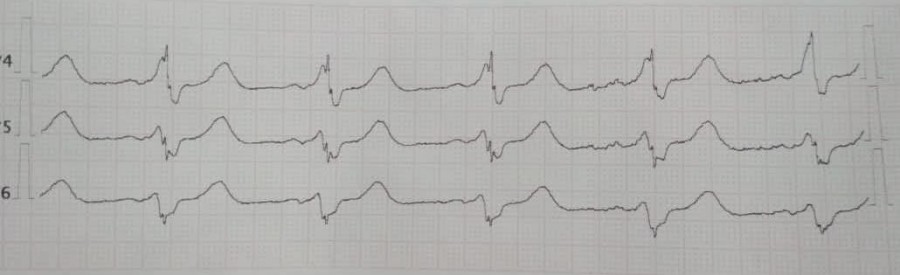

ФП при ВПВ

Вложения: